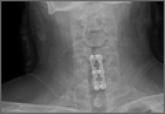

Novel Intraoperative Technique to Visualize the Lower Cervical Spine: A Case Series

Visualization of the lower cervical spine with a lateral radiograph poses a challenge secondary to encroachment of the shoulders.